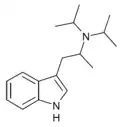

| NiPT | artificial | H | H | CH(CH3)2 | N-isopropyltryptamine | 14121-10-9 |

| MiPT | artificial | H | CH3 | CH(CH3)2 | N-Methyl-N-isopropyltryptamine | 96096-52-5 |

| DiPT | artificial | H | CH(CH3)2 | CH(CH3)2 | N,N-diisopropyltryptamine | 14780-24-6 |